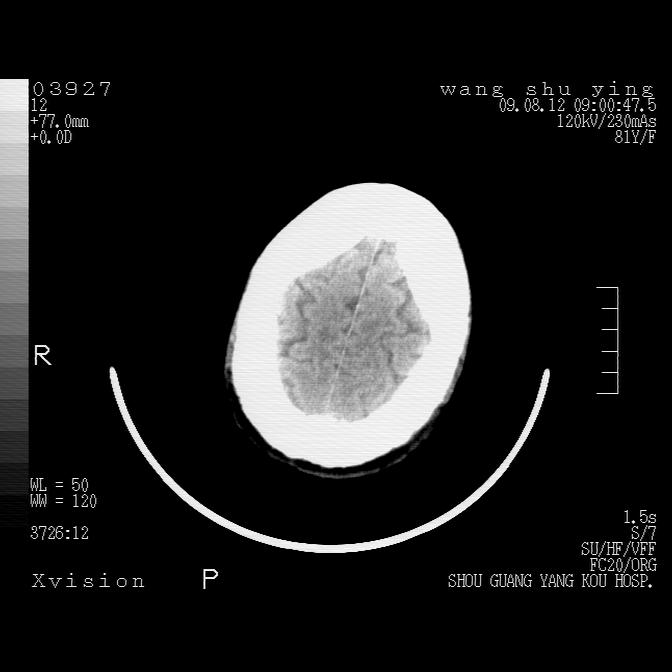

以下是引用帅河马在2009-8-12 12:59:00的发言:[br]两肺感染性病变伴双侧胸膜肥厚。[br]左侧甲状腺腺瘤不除外。[br]腹水+心包积液。[br][br][本贴已被 帅河马 于 2009-8-12 13:14:32 修改过]

以下是引用sdzyy在2009-8-12 18:17:00的发言:[br]两肺感染性病变伴双侧胸膜肥厚。[br]左侧甲状腺腺瘤不除外。[br]腹水+心包积液。[br]支持